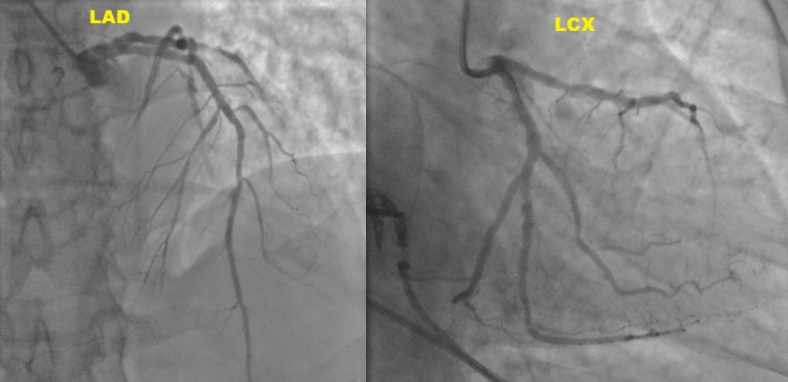

Coronary angiogram revealed mild LAD stent ISR, RCA CTO and severe obtuse marginal (OM) branches disease. PCI of the OM branches with drug-coated balloons was performed. Subsequently electively admitted for stage PCI to RCA CTO.

Dual access via right radial and femoral arteries. Failed to cross antegradely the proximal cap CTO using UltimateBros3 and Fielder XT-R guidewires / Corsair Pro, and retrogradely via septals collateral. Initially decided to abandon the procedure as deem small RCA vessel size. Unfortunately noted coronary perforation at proximal RCA CTO site, temporary tamponade with microcatheter. Retrograde Suoh3 wire via LAD epicardial collateral successfully crossed the distal cap of proximal RCA CTO, however, Caravel microcatheter unable to pass through the distal RCA branch for better support. Gladius EX14 guidewire supported with Corsair Pro microcatheter swiftly crossed the proximal cap antegradely (using the Suoh3 as the guide from retrograde) successfully till distal RCA branch. Caravel and Suoh3 removed retrogradely without complication. Predilate the RCA (prolonged balloon inflation) using SC 2.0x15mm (6-8atm, 3mins each) - to facilitate the plaque sealing of the perforation site. IVUS performed confirmed the wire in the true lumen. Stented with 2 overlapping DES 2.25x33mm (nominal) and 3.0x33mm (nominal). Noted the stent was from RCA-acute marginal branch, distal RCA was smaller vessel. Post-dilated distal stent with NC 2.5x15mm (nominal) while proximal stent with NC 3.0mm and NC 4.0mm. IVUS performed good stent apposition/expansion, with satisfactory MSA. Good angiographic result, TIMI 3 flow, no dissection/perforation noted. No pericardial effusion from echocardiography.